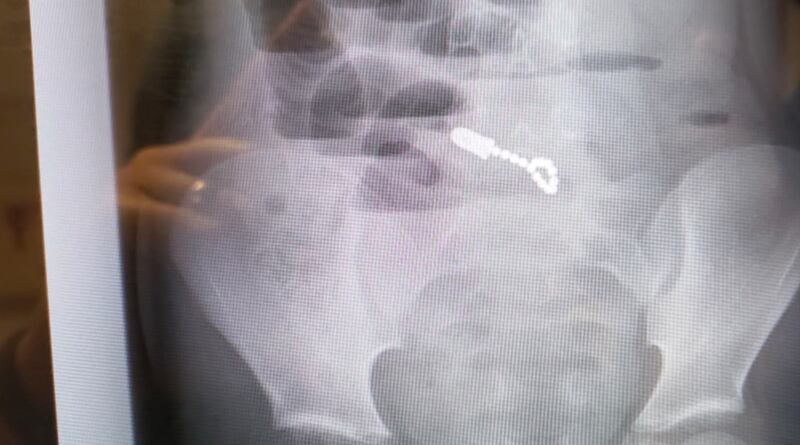

On Nov. 3, his parents took him to the emergency room at Primary Children's Hospital where doctors rushed to find out what was causing Mikah's symptoms. They ran bloodwork, gave Mikah pain medication and did an X-ray.

"When they took the X-rays, they thought he had maybe a metal zipper or something in his pants because it was showing the magnets on the X-ray. But we didn't know he had swallowed them, and he didn't know he'd swallowed them," she said.

There they were — 14 magnets, each the size of a pinhead, clumped together in his intestines and causing life-threatening injuries. Doctors rushed Mikah into an emergency surgery to remove them and to repair the damage.